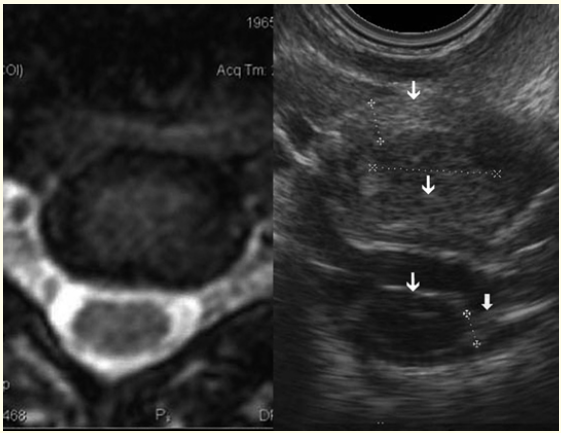

Ultrasound Findings in Cervical Radiculopathy

Rizvan Ya. Abdullaiev, Faina I Kulikova, Tatyana L Kutsyak, Victoria V Stus, Anna V. Logvinenko, Larisa V Rusan, Sergey G Gorodetsky, Alla I Rebyakova and Elena V Spirina. 15(1): 11-16.